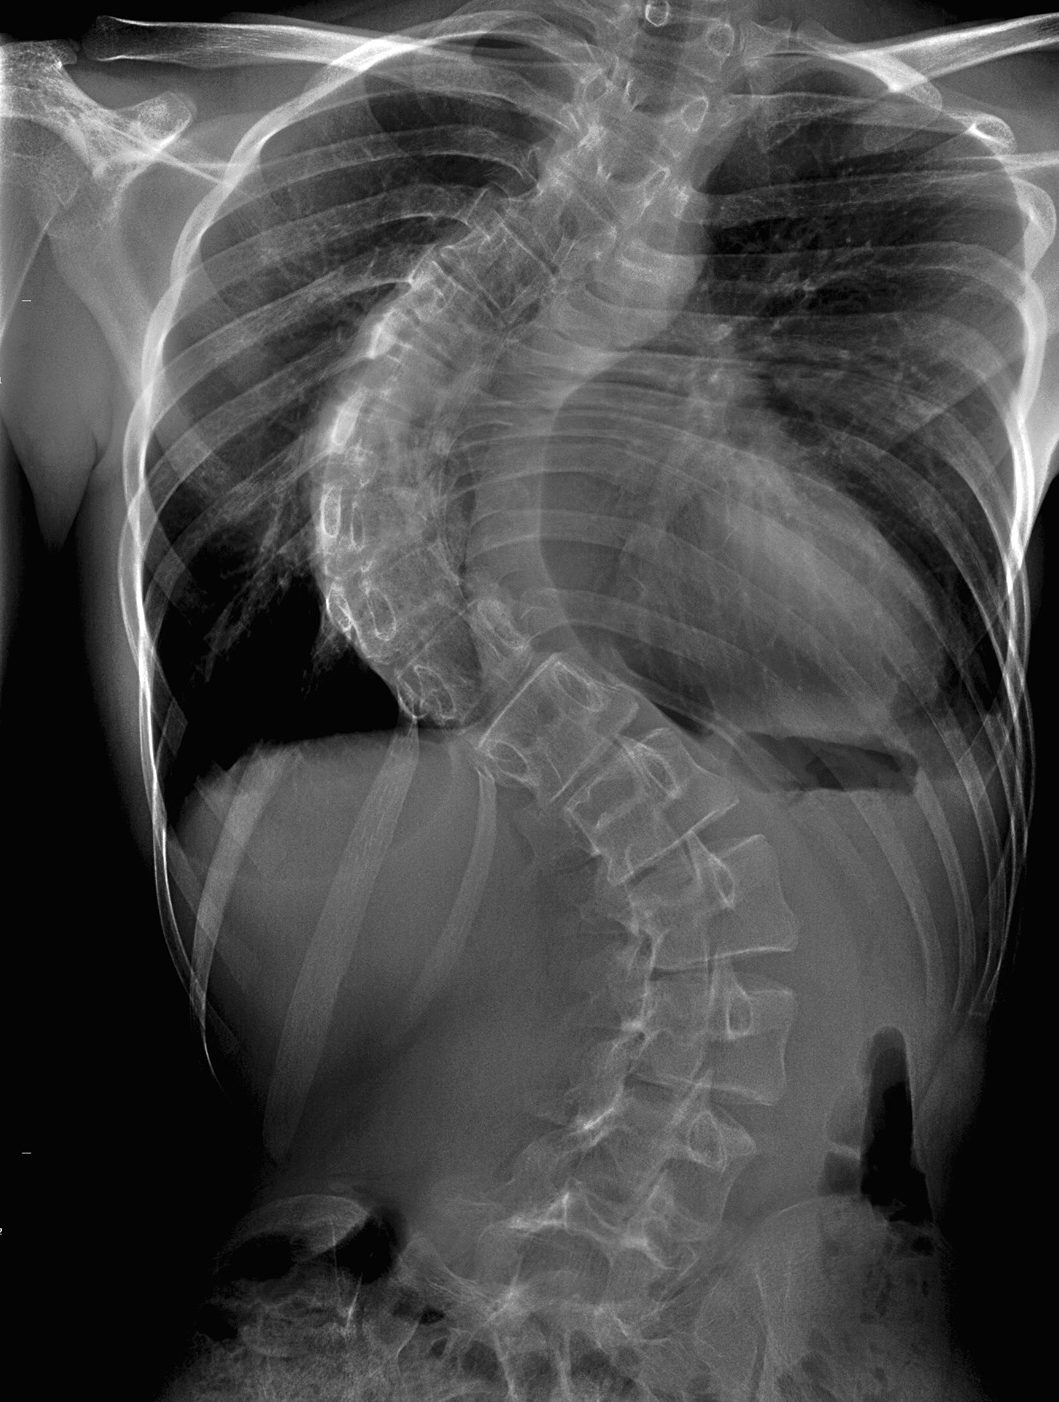

Un adolescent de 16 ani, din județul Botoșani, are nevoie de ajutor pentru a lupta cu o boală grea. Mario, din Bucecea, a fost diagnosticat cu scolioză, o boală întâlnită frecvent, care însă, în cazul lui a luat o amploare de o gravitate ieșită din comun. Coloana vertebrală a baiatului s-a înclinat la 98 de grade, iar acum doar o operație costisitoare la Spitalul Monza din București îl mai poate salva și îi poate reda viața cât de cât normală. Operația costă însă 23.000 de euro, bani pe care familia nu îi are.

„Dacă poartă corset și o bluză, malformația nu se vede așa tare, dar puteți vedea pe radiografie cum este. Dacă nu se intervine din punct de vedere chirurgical, atunci baiatul meu nu va putea să aibă o viață normală de adult. Doctorii sunt optimiști și spun că operația va avea succes, însă costurile sunt enorme pentru noi”, spune tatăl băiatului.